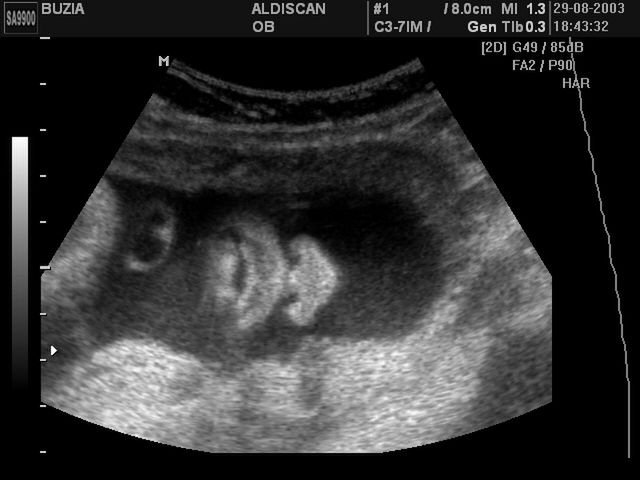

Ten tydzień to nie tylko początek wymarzonego (bo uboższego w dolegliwości ciążowe) okresu ciąży, ale też moment, gdy przyszli rodzice mogą wreszcie poznać płeć dziecka. Męskie narządy płciowe wykształcają się już w pierwszym trymestrze, jednak o płci można mówić dopiero teraz, gdy rozwijać zaczynają się żeńskie organy. W tygodniu jajniki wędrują do miednicy, można więc podczas badania USG odczytać, co dzidziuś ma – jak to kolokwialnie ujmują ciężarne – pomiędzy nogami. Oprócz tego widoczne są już włoski na głowie i meszek na ciele dziecka, powstaje otwór odbytowy, a tarczyca rozpoczyna produkcję hormonów.